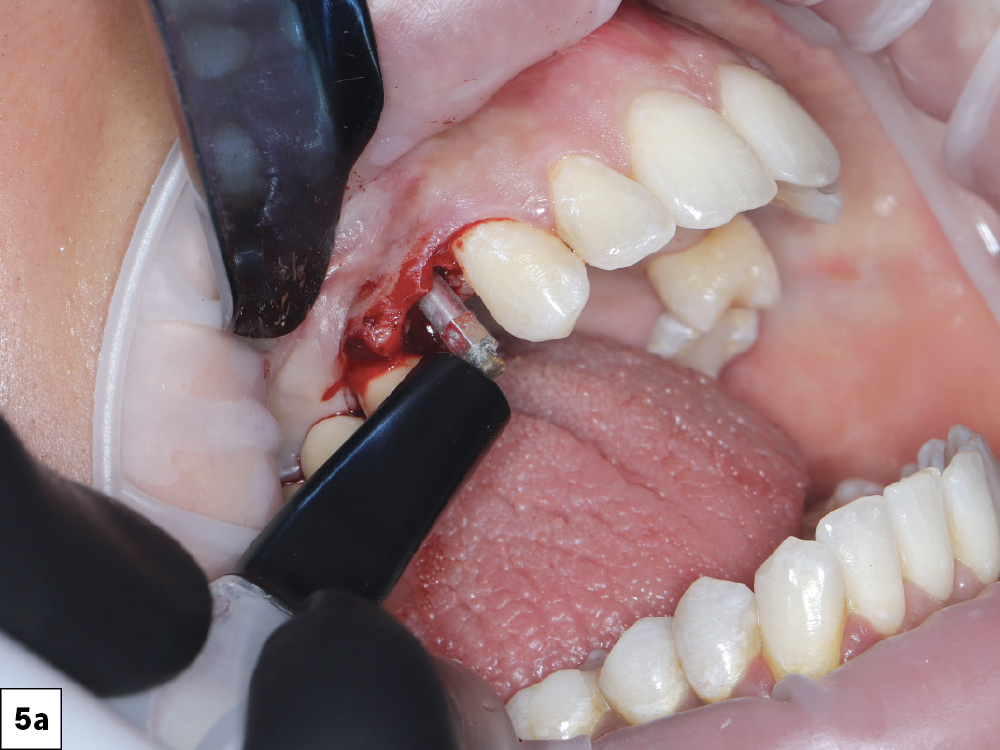

Resonance Frequency Analysis (RFA) was used to confirm an Implant Stability Quotient (ISQ) appropriate for immediate loading

Resonance Frequency Analysis (RFA) was used to confirm an Implant Stability Quotient (ISQ) appropriate for immediate loading-b

Resonance Frequency Analysis (RFA) was used to confirm an Implant Stability Quotient (ISQ) appropriate for immediate loading-c

Figures 5a–5c: Resonance Frequency Analysis (RFA) was used to confirm an Implant Stability Quotient (ISQ) appropriate for immediate loading.